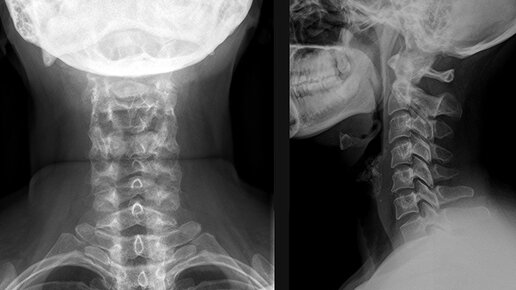

Для чего назначают рентген шейного отдела позвоночника? Шейный отдел – это самая незащищенная область позвоночника. А сидячий образ жизни, свойственный современному человеку, имеет сильное негативное влияние на эту область. А так как этот отдел позвоночника, является самым подвижным, то этот отдел наиболее подвержен различным повреждениям и снижению двигательной функции. Нарушения в шейном отделе могут повлиять на работу головного мозга, органов зрения и слуха. Сделать правильную диагностику различных нарушений, поможет рентгенография шейного отдела позвоночника...

При возникновении подозрения на травму или для диагностирования патологического процесса пациентам назначают рентген шейного отдела позвоночника. Он позволяет увидеть любые изменения в опорно-двигательном аппарате. Данный метод диагностики наиболее распространен, ведь необходимое рентгенологическое оборудование есть в каждой поликлинике. Преимущества проведения рентгена Рентген – распространенный и недорогой способ определения патологий опорно-двигательного аппарата. Он популярен при выявлении патологических процессов в позвоночнике, грудном отделе и шее...